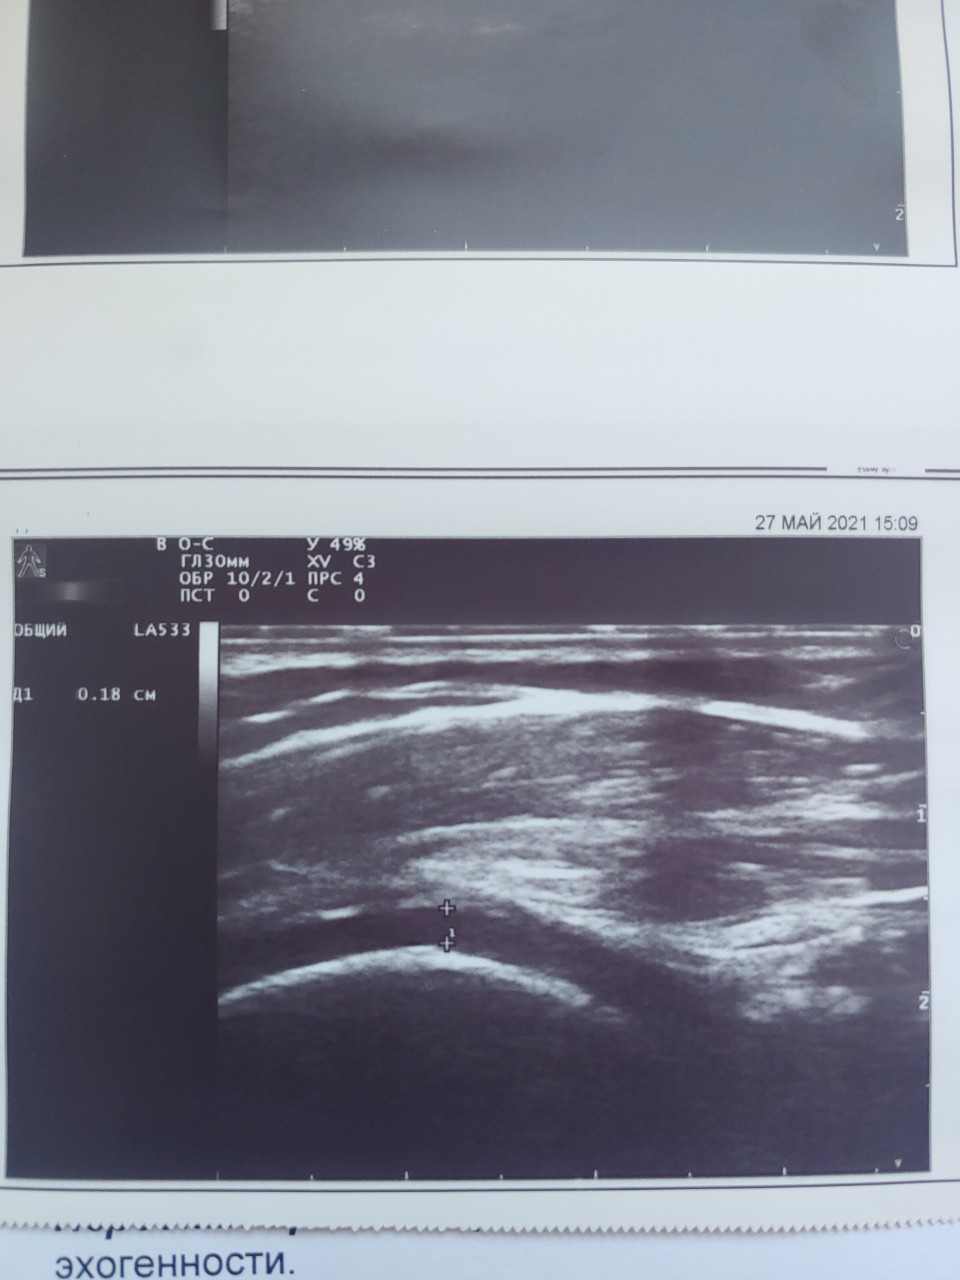

УЗИ коленных суставов Вам не делали?

Благодарю за внимание! Делали, в выписке если Вам не сложно можно посмотреть (загружены сканы к вопросу)

Прошу прощения, не заметил. В любом случае, они не делали исследование в режиме энергетического допплера, а это при подозрении на артрит самое главное.

Здравствуйте, уважаемый Андрей Анатольевич! Можно попросить Вас оценить состояние суставов сына. Сделано УЗИ в режиме Допплера (если это действительно так) Сейчас жалоб нет, единственное, что или просто боится сесть на корточки, или не позволяют ощущения. Говорит что не может до конца согнуть колени (угол сгиба примерно 45-50 градусов). Но, например, у меня самого в колене нога тоже до конца не сгибается, 30-40 градусов. СРБ и СОЭ сейчас, как и раньше, в норме. Очень хочу перевести лечение с метотрексата на Сульфасалазин + Метилпреднизолон по Вашей схеме.

Здравствуйте! Высылаю описание УЗИ.

По узи у ребёнка нет признаков артрита. Энтезиты более характерны для псориатического артрита.